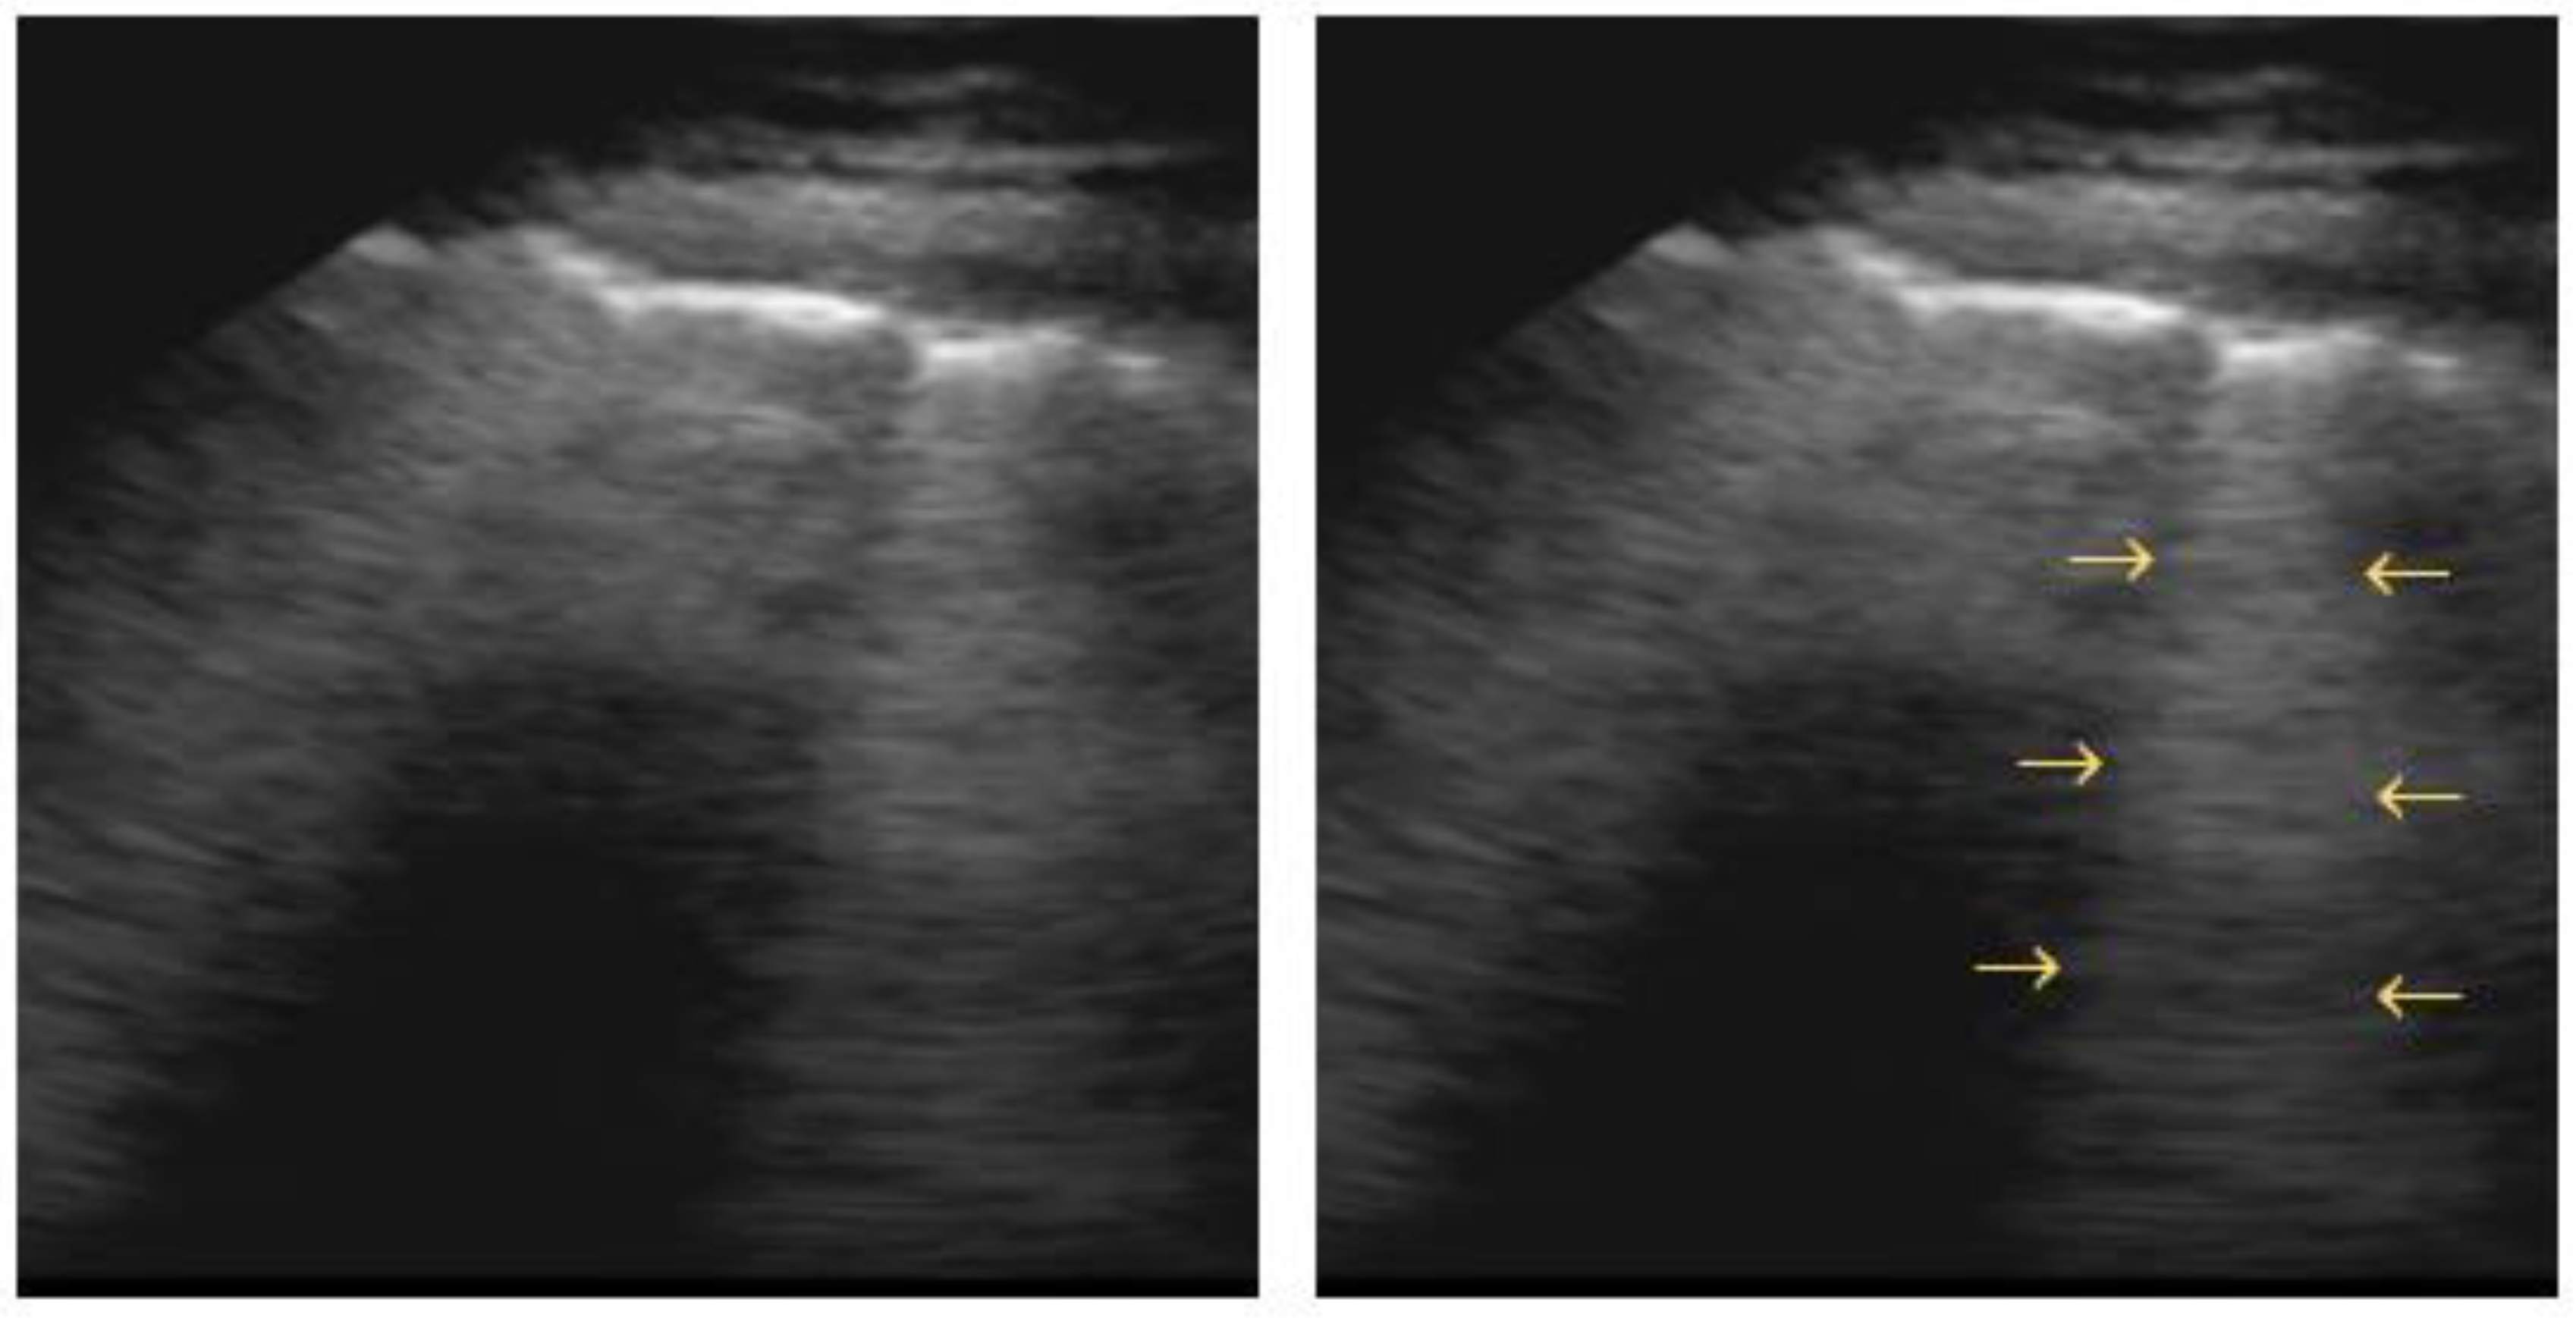

4.2. Interstitial Syndrome

- Pulmonary fibrosis, with B-lines in a diffuse, more or less homogeneous distribution, with an irregular pleural line and often, subpleural abnormalities [63];